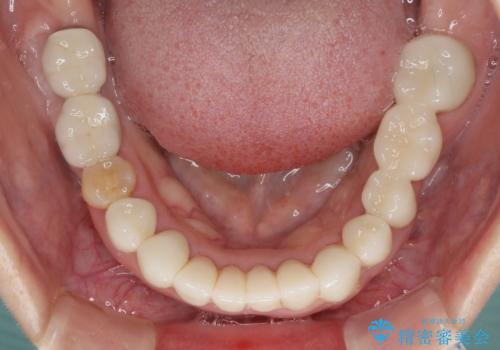

- 下顎の前歯に激痛を覚えて来院された患者様です。

取り急ぎ下顎前歯数歯の根管治療を、銀座しらゆり歯科医院長の林先生にお願いし、それ以外に気になっている、不自然な色調のクラウン、金属部分が見えてブラッシングがしにくいインプラント補綴、口元の突出感、出血のしやすい歯周ポケットなど、全てを解決するための治療を行うこととしました。

期間と費用はかかりましたが、気になっていた部分全てを改善でき、患者様には大変満足していただきました。